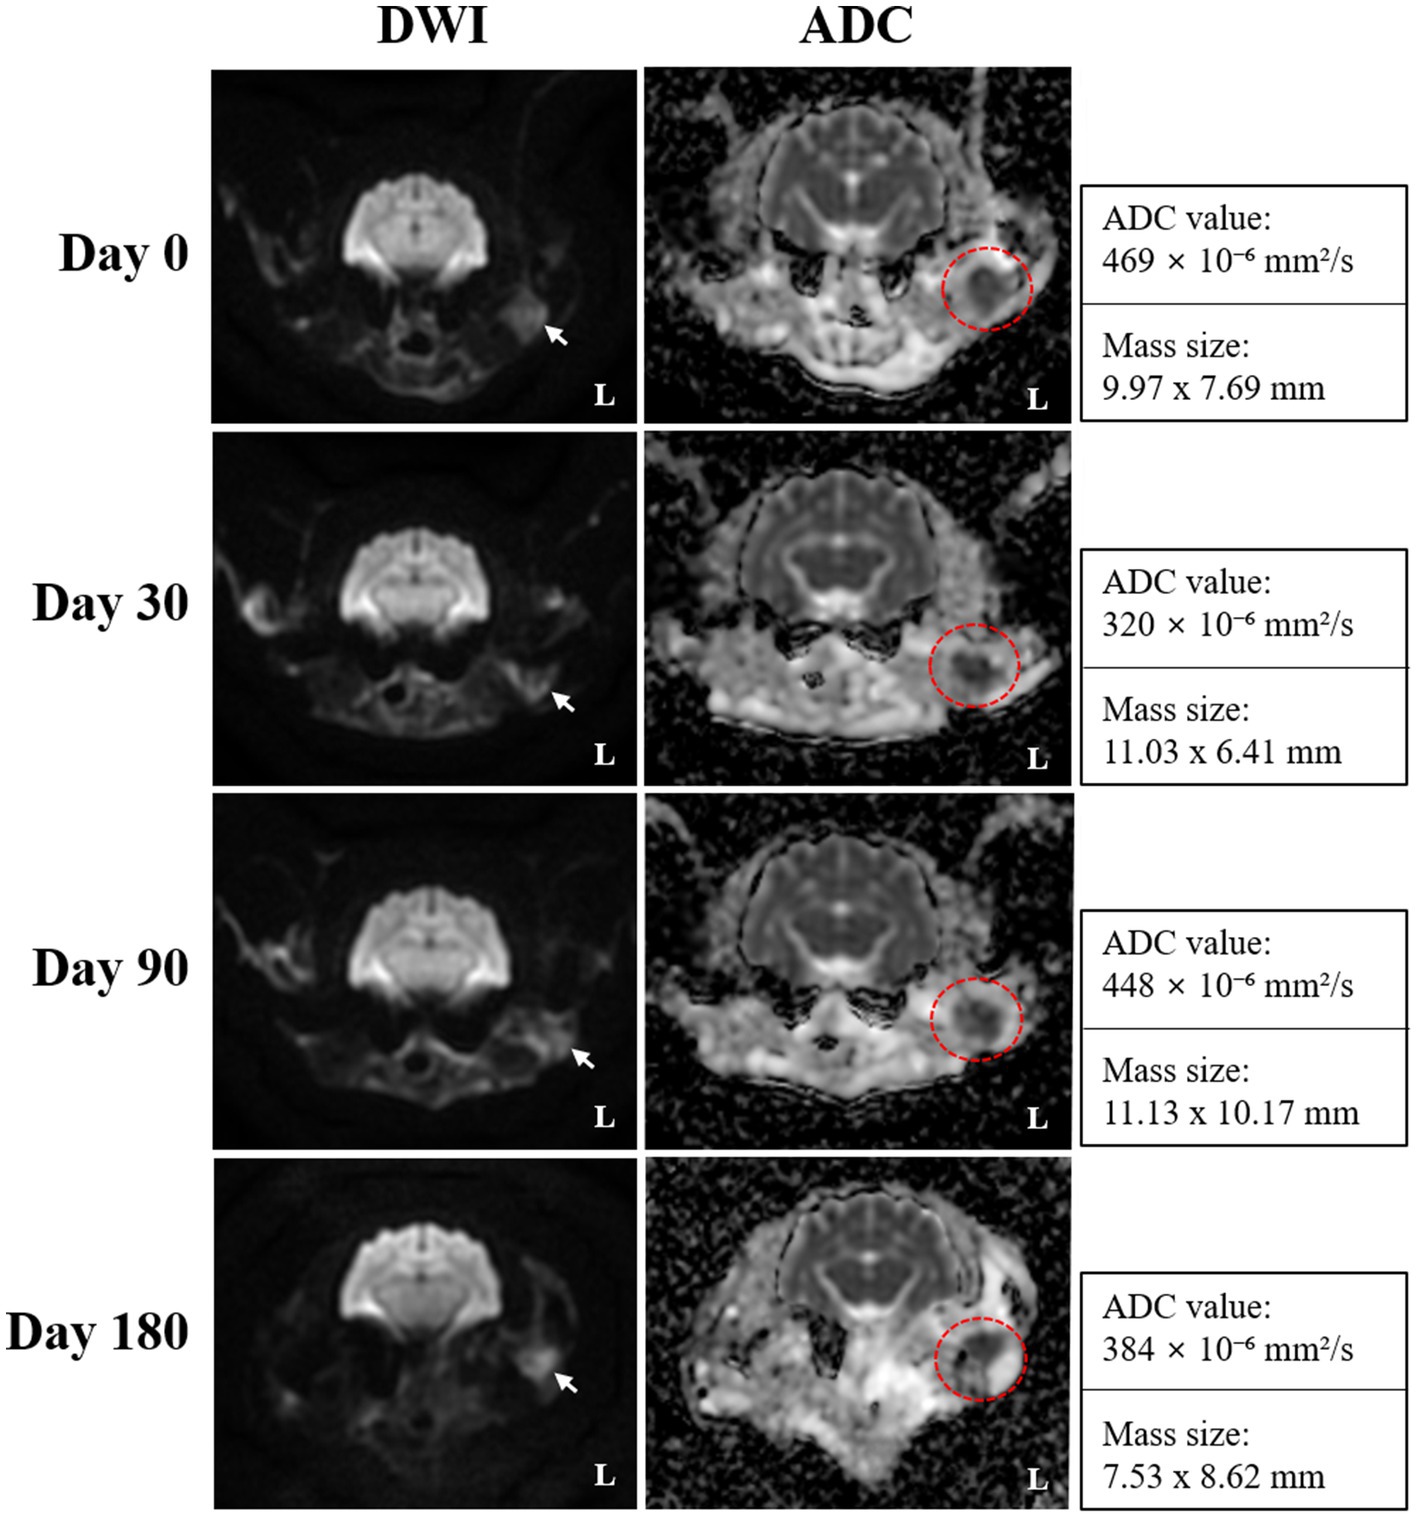

On day 0 (radiotherapy completion), cross-sectional imaging demonstrated a significant reduction in the size of the mass in the left external ear canal (Figure 3). However, residual soft tissue remained within the external auditory canal, and although the previously invasive component extending into the left parotid and mandibular regions regressed markedly, it continued to exhibit strong contrast enhancement. The residual lesion displayed poorly defined margins and induced medial displacement and compression of the adjacent masseter muscle. Additionally, findings suggestive of concurrent otitis externa included thickening and calcification of the external ear canal wall, along with a small volume of luminal fluid. The left mandibular, medial retropharyngeal, and prescapular lymph nodes remained enlarged and rounded, although they were notably reduced in size compared to pre-treatment imaging. The right medial retropharyngeal lymph node remained mildly enlarged. MRI revealed hyperintense lesions on DWI and corresponding hypointense regions on ADC maps in the left mandibular and parotid regions, which visibly decreased in both extent and intensity (Figure 4). The mean ADC value and size of the mass were measured at 469 × 10−6 mm2/s and 9.97 × 7.69 mm, respectively. On day 30, further regression of the mass within the external auditory canal was noted on conventional CT and MRI.

Figure 4. Serial diffusion-weighted imaging (DWI) and apparent diffusion coefficient (ADC) mapping obtained on days 0 (radiotherapy completion), 30, 90, and 180 for monitoring radiotherapy response in the present case. Transverse DWI and ADC images reveal a focal area of persistent diffusion restriction, which is characterized by hyperintensity on DWI (white arrows) and corresponding hypointensity on ADC maps (red dotted circles), and remained visible throughout the follow-up period, suggesting the presence of residual tumor tissue despite an overall favorable response. ADC mapping provided improved delineation of the lesion margins, and the persistently low ADC values indicated sustained high cellularity within the residual lesion.

Nevertheless, contrast enhancement and indistinct margins persisted in the left parotid and mandibular regions. The mandibular and retropharyngeal lymph nodes continued to show a reduction in size, with only mild enlargement remaining. However, the left prescapular lymph node was notably enlarged compared to the previous scan. On DWI and ADC imaging, the signal intensity and size of hyperintense lesions on DWI remained similar to those on day 0. The mean ADC value and size of the mass was calculated at 320 × 10−6 mm2/s and 11.03 × 6.41 mm, respectively. On day 90, no significant changes in the size, extent, or imaging characteristics of the residual lesion were observed compared to day 30. Severe enlargement of the left prescapular lymph node, along with the mandibular, medial, and lateral retropharyngeal lymph nodes, remained similar. On DWI and ADC imaging, hyperintense lesions on DWI also remained stable. The mean ADC value and size of the mass were recorded at 448 × 10−6 mm2/s and 11.13 × 10.17 mm, respectively. Persistent findings in the left parotid and mandibular regions suggested the presence of residual neoplastic tissue.

On day 180, although the size and extent of the residual mass on conventional CT and MRI showed no remarkable changes, there was marked disease progression, characterized by marked enlargement of multiple lymph nodes, including the left medial retropharyngeal, left prescapular, and right medial retropharyngeal nodes. Furthermore, contrast enhancement in the left parotid and mandibular regions increased, indicating potential tumor recurrence or progression. Concurrent left-sided otitis media was newly identified. The mean ADC value and size of the mass was measured at 384 × 10−6 mm2/s and 7.53 × 8.62 mm, respectively. Based on serial CT and MRI evaluations, the tumor response in this case was classified according to the Veterinary Cooperative Oncology Group (VCOG) response evaluation criteria for solid tumors in dogs (v1.0) (15), using the maximal diameter of the primary lesion as the measurement parameter. Compared with the pretreatment baseline, the tumor size at day 0 showed more than a 50% reduction, fulfilling the criteria for partial response (PR). By day 30, an additional 30% decrease relative to day 0 was observed, resulting in an overall reduction of approximately 80% compared with baseline, consistent with a continued PR. At day 90, the lesion showed minimal further reduction (~10%) compared with the nadir, maintaining a partial response (PR). By day 180, the lesion had increased by approximately 20% from the nadir, accompanied by marked enlargement of regional lymph nodes, meeting the criteria for progressive disease (PD).